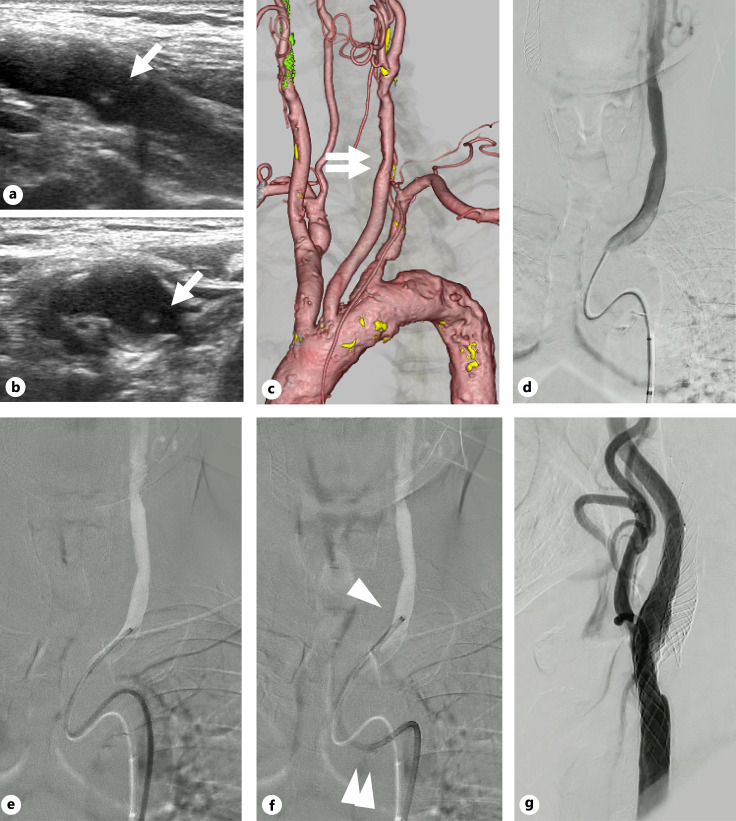

Introduction: During carotid artery stenting (CAS), safe navigation of the guiding catheter (GC) is essential for the success of procedures. However, in cases where stenosis or floating thrombi are located in the common carotid artery (CCA), especially for proximal lesions, advancing the GC without touching the lesions is often difficult. We describe a preliminary experience of the "no-touch" technique for navigating the GC to the CCA using an inner catheter with a specifically designed shape and stiffness optimized to overcome tortuous anatomy.

Methods: We retrospectively reviewed CAS procedures involving the "no-touch" technique for treating stenotic lesions in the CCA. A 4-Fr Newton-shaped stiff catheter was positioned in the CCA. Given its high stiffness and dedicated shape, contact with the lesser curvature of the aortic arch absorbed kickback force. Then, a 6-Fr intermediate catheter and an 8- or 9-Fr balloon GC were coaxially advanced in sequence to the target position without guidewire support, ensuring "no-touch" with the plaques. Patient characteristics, aortic arch type, lesion location, and periprocedural complications were recorded.

Results: The technique was applied to eight procedures (six left-sided lesions) in 7 patients (median age, 76 years; six men) among 53 CAS procedures performed on 49 patients. Lesions were located at the proximal CCA (four procedures) or the carotid bifurcation (four procedures). Three patients had floating thrombi, and four had type III aortic arches. GCs were successfully navigated without touching the lesions in all cases, with no periprocedural complications.

Conclusion: The "no-touch" technique with a Newton-shaped stiff catheter is useful and feasible for navigating the GC in treating stenotic lesions in the CCA, particularly with tortuous anatomy, proximal lesions, and vulnerable plaques.